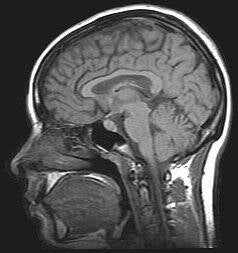

See above: cranial MRI scan

A prominent use of nanotechnology in medicine is for enhanced medical imaging - allowing us to gain better insight into the human body and make diagnosis on illnesses in an increasingly non-invasive way. A general way in which medical imaging aims to develop is through improving the ‘contrast’ of images, in other words, the ability to differentiate between different tissues in the body, which are very densely packed and often similar looking. A ‘contrast agent’ is used to improve this aspect - and this is where nanotechnology is applied. An example of nanoparticles used as contrast agents is SPIONs - or superparamagnetic iron oxide nanoparticles - in MRI imaging.

A simplified way in which MRI works is by sending all of the protons in your body a strong magnetic pulse to align them, change their alignment with radio waves, before allowing them to return to their original positions - this stage causing them to release energy as they do so, unique to the type of tissue they are present in. This final stage is sometimes referred to as the ‘relaxation stage’, and SPIONs create a stronger magnetic field which causes alterations in the energies of protons belonging to water, shortening their relaxation stage - making some areas of the image produced darker; more detailed. Another benefit of using SPIONs is their ‘superparamagnetic’ property, which means they lose their magnetism after being removed from the external magnetic field of the MRI scanner - and this reduces the chances of artefacts in the image, which are essentially fake details produced by the imaging process. They are also very compatible with body cells, and can be coated with polymers to ensure they minimise damage and do not accumulate in the body whilst present inside. Overall, this improved imaging could thus help us spot cancers and lesions in earlier stages, and its less-harsh presence in the body means it could be utilised for a larger variety of cases.